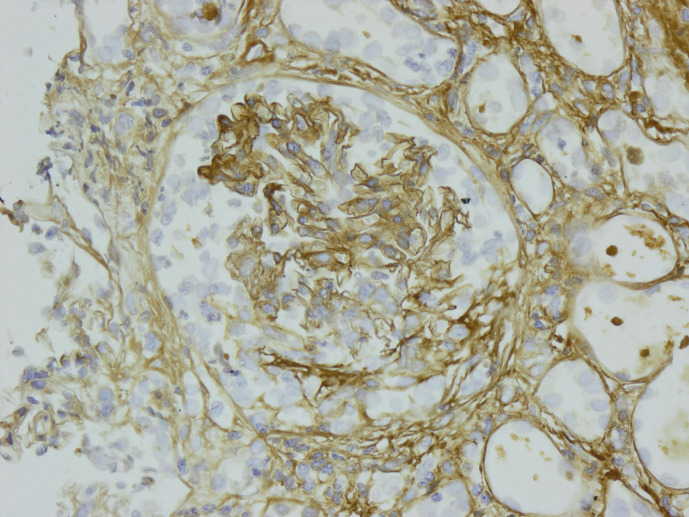

Case presentation: We present the case of a 67-year-old man with rapidly progressive glomerulonephritis requiring haemodialysis at presentation. Serological testing was positive for anti-myeloperoxidase and negative for IgG anti-GBM antibodies. Kidney biopsy revealed necrotizing crescentic glomerulonephritis with linear staining of IgA along the GBM. He was treated with a combination of immunosuppression and plasma exchange and was able to become dialysis-independent.

Conclusion: To our knowledge, this is the first documented "double-positive" IgA anti-GBM disease and ANCA-associated glomerulonephritis.